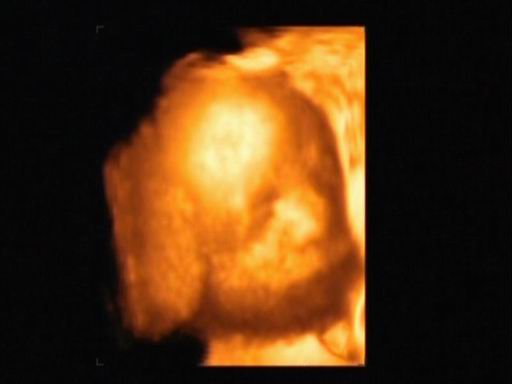

Mégsem múlt héten voltam dokinál, mert elmaradt a rendelés örültem....Így tegnap voltam dokinál minden rendben, meg du. 4D-n voltunk. Tényleg fiú és jó nagy a korához képest,több, mint egy héttel nagyobb 860 gr. :D Majd próbálok kivenni a videóból képet.